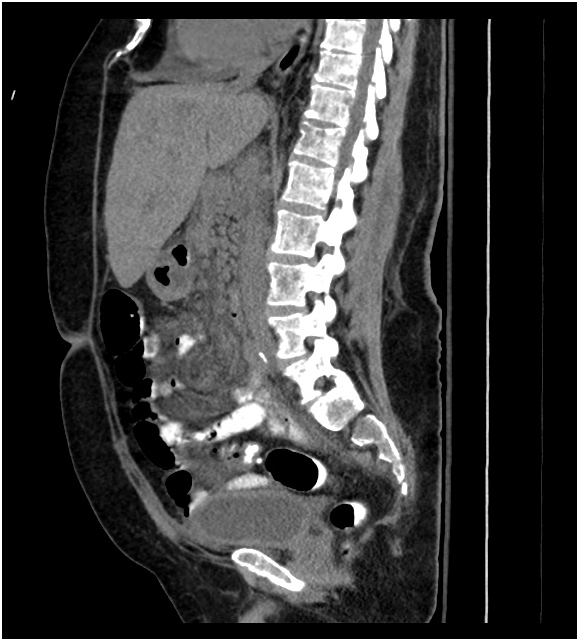

This is a case of a 68year-old male with a past medical history of seizures, hyperlipidemia, and right cerebral vascular accident in 2009 with residual left sided visual field deficits. Ten months before presentation, the patient had a CT scan of the abdomen for recurrent epigastric pain which showed mesenteric lymphadenopathy. This was followed by imaging of the chest which showed scattered, centrally located, bilateral solid pulmonary nodules which measured less than 4mm. Biopsy of retroperitoneal lymph nodes at that time showed no evidence of malignancy. Subsequently, he presented to the emergency department with a several week history of worsening back pain and altered mental status. Initial blood work showed evidence of pre-renal acute kidney injury and hypercalcemia, serum calcium 15.7mg/dL (normal 8.5-0.5mg/dL). Hemoglobin at presentation was 10.8g/dL (normal 14.0–18.0g/dl). White blood cell count of 21.82k/uL (normal 4.0-11.0k/uL). Platelet count was 148 k/uL (normal 150.0–450.0k/uL) and creatinine of 1.4mg/dL (normal 0.7–1.3mg/dL). After volume resuscitation calcium returned to baseline of 8.8mg/dL and creatinine returned to baseline of 0.7mg/dL. MRI of the thoracic and lumbar spine showed a diffusely low vertebral body marrow signal concerning for myelodysplastic process. CT scan of the chest, abdomen and pelvis showed multiple lyric lesions involving the thoracic vertebrae, scapulae and ribs concerning for multiple myeloma (Figure 1). The patient had a bone scan which was negative. Bone marrow biopsy was performed and showed high-grade metastatic neuroendocrine tumor. Immunohistochemical staining for synaptophysin, CD56, and cytokeratin was positive within the tumor cells (Figure 2). In addition, chromogranin was weakly positive within a subset of tumor cells. Tumor cells were strongly positive for thyroid transcription factor-1 (TTF-1). Flow cytometry showed no significant plasma cell population and no evidence of B-cell clonality. The patient was treated with Carboplatin (AUC 4), which was escalated to AUC of 5 during the second cycle, and Etopside (80mg/m2). He also suffered from severe weakness requiring nursing home placement. Repeat imaging after 3 cycles of chemotherapy showed progressive disease with a new lesion in the spleen (1cm) and progression of compression deformities of T8 and T12 as well as a new right anterior 6th rib fracture. Goals of care were discussed and comfort care measures were initiated. By the time of submitting this article, 4months after the diagnosis was made, the patient remains alive and receiving palliative care.

Figure 1 CT chest of the abdomen and pelvis showing vertebral lytic lesions.